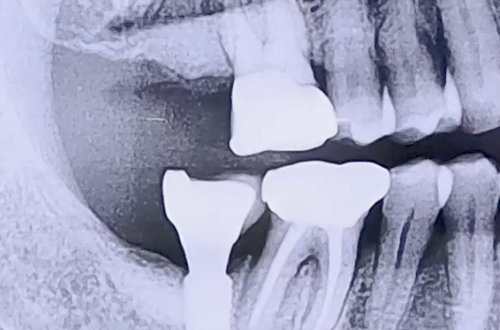

AFTER

이 상태로 임플란트를 식립할 수는 없기 때문에 우선 뼈이식을 통해서 잇몸뼈를 충분히 보강하고 단단해지기까지 기다렸다가 임플란트를 식립하는 지연식립으로 계획하시고, 뼈이식 치료를 우선적으로 진행하신 케이스입니다.